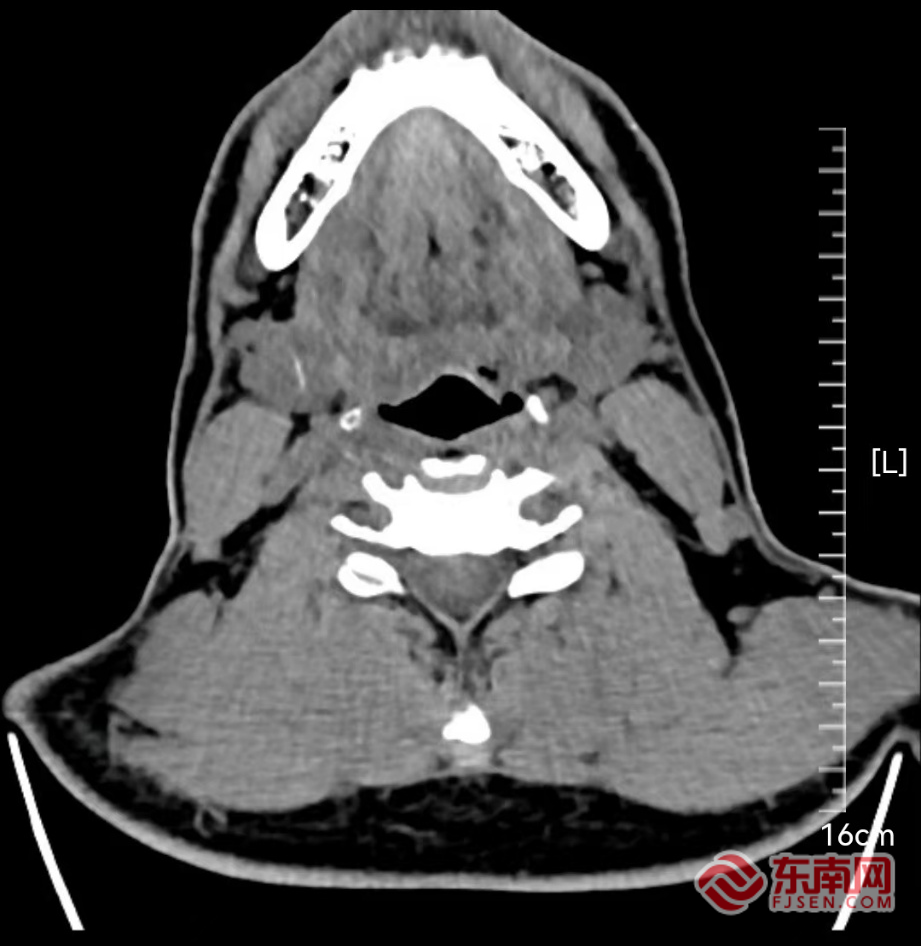

1个月前,孙先生吃饭时不慎被鱼刺卡喉,当时便感觉咽部刺痛、有异物感,前往外院检查却没找到鱼刺的踪迹。想着可能鱼刺已经下去了,孙先生便没再重视,可咽部的疼痛感、异物感却始终存在,整整困扰了他1个月。近期,咽痛依旧的孙先生再次到医院做CT检查,却发现鱼刺竟然“游走”到了下颌下腺(位于下颌下区的重要唾液腺)区域。

术前影像图。宁德市医院供图

为求稳妥治疗,孙先生来到宁德市医院耳鼻咽喉头颈外科就诊。副主任医师张茂华接诊后,结合CT影像仔细评估发现,鱼刺已侵入下颌下腺内部。“由于异物长期刺激,腺体局部炎症反应明显,若不及时处理,可能引发更严重的感染,甚至异物进一步游走到颈部的大血管引发大出血。”张茂华介绍。经综合判断,医生决定为孙先生实施下颌下腺切除术,以彻底清除异物并解决腺体受侵问题。